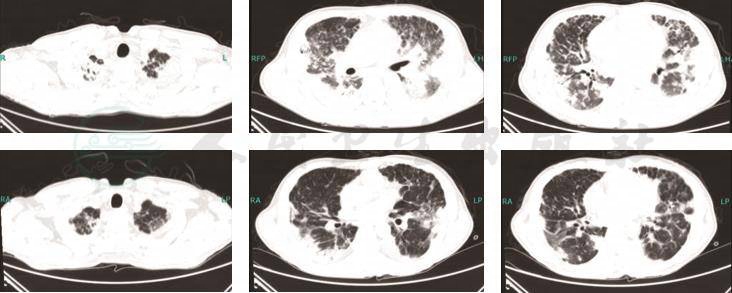

7.入院前3次胸部CT对比(2017年4月3日,2017年4月7日,2017年4月17日)双肺弥漫性病变,中外带病灶较前增多,考虑感染可能性大(图1)。

图1 胸部CT

(由上至下分别是2017年4月3日,2017年4月7日,2017年4月17日)

4.肺部CT示双肺病变,多发结节及斑片渗出影,逐渐增多融合实变。